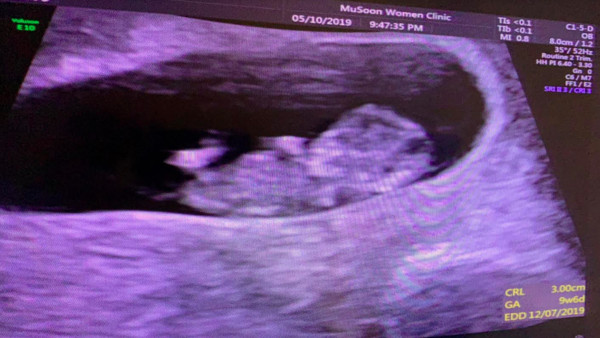

▼小马夫妻告别宝宝多恩。

親愛的朋友們,此刻的我抱著沉痛的心情,要告訴大家非常遺憾的消息,7/23我陪同太太產檢時,超音波檢測不出寶寶心跳,經醫生檢查各項數據,判定寶寶是因綜合發育不完全,生理性自然淘汰!近20週的生命,就這麼離開了我們。 這突如其來的噩耗,震撼了...